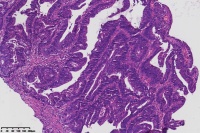

中分化腺癌?

性别

女

年龄

67岁

临床诊断

一般病史

直肠占位

标本名称

大体所见

腺癌(低一中 分化)

中分化腺癌